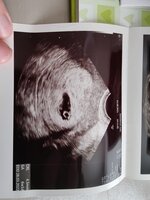

Täällä käyty tänään neuvolan tarjoamassa varhaisultrassa. Löytyi elävä pieni. Viikkoja vastasi 9+5